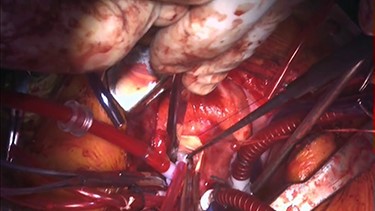

Under general anesthesia, cardiopulmonary bypass was established by ascending aortic and bicaval cannulation. After transverse aortotomy, LVOT was exposed through the aortic valve by retracting the aortic wall. The cardiac muscle hypertrophy with abnormal bundle-like cardiac muscle was observed in the LVOT, including the septal area. The hypertrophied area was scooped up by a nerve hook and cut by scalpel (Fig. 2 and Video 2). Next, the left atrium was incised and the mitral valve was exposed. The edge-to-edge technique with a suture of the A2–P2 area was performed for mitral valve reconstruction. Postoperative recovery was uneventful, and echocardiography revealed improved LVOTS with 1.7-m/s peak velocity and no MR or mitral stenosis (Fig. 3 and Video 3).

Intraoperative findings. The abnormal muscle band is cut by scalpel, and edge-to-edge repair of the mitral valve is performed.